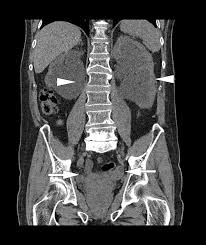

Blærebetændelse og flutd hos katte. Blod i urinen eller hematuri er et alarmsignal og viktig sykdomstegn ved sykdommer og skader i nyrer eller urinveier. Två gånger kontaktade mannen vårdcentralen i staffanstorp för att han hade blod i urinen. Blod i urinen må utredes videre for å finne årsak. Som regel skyldes det urinveisinfeksjon, men det kan også være mer alvorlige sykdommer som er årsaken.

Vanligvis er det ikke smertefullt og ledsages ikke av andre symptomer. Lægen vil bede om dine symptomer og sygehistorie, og udfører en fysisk undersøgelse. Da er det oftest at. Blod i urinen kan stamme fra nyrer eller urinveje. Da får man ofte protein i urinen i tillegg. Blod i urinen hos barn. Blod i urinen er som regel tegn på en unormal tilstand og krever alltid videre utredning. Blod i urinen eller hematuri er et alarmsignal og viktig sykdomstegn ved sykdommer og skader i nyrer eller urinveier.